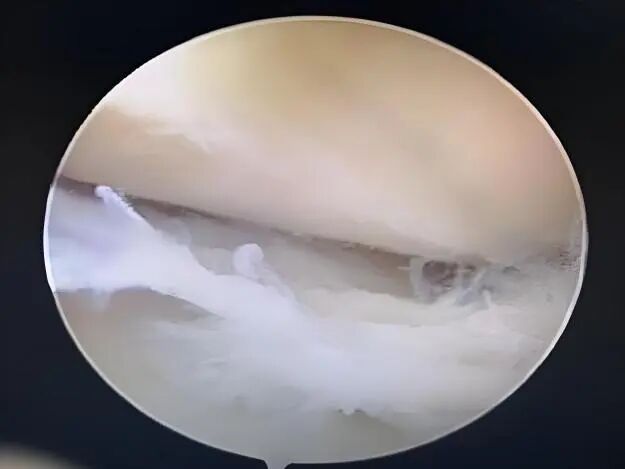

1.建立膝关节前内侧、前外侧入路,插入关节镜,全面探查膝关节内结构,重点观察半月板后角撕裂部位、形态、范围,确认撕裂边缘整齐度及是否存在软骨损伤。

2.用生理盐水冲洗关节腔,清理关节内积血、炎性组织及撕裂边缘破损组织,为缝合操作提供清晰视野。